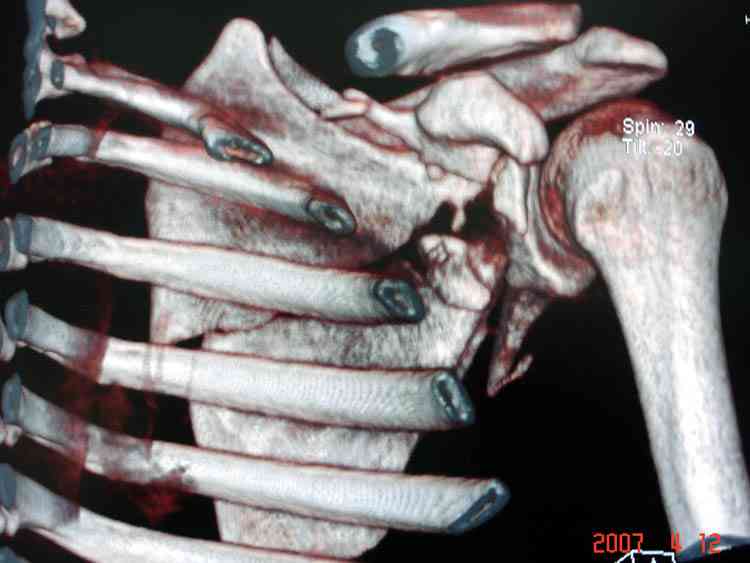

К-томографические и Трехмерные(3D)снимки крайне важны для определения внутрисуставных переломов и классификации.

Кроме анатомической классификации, переломы лопатки делятся на стабильные и нестабильные, внутри- и внесуставные и с вовлечением суставной поверхности.

Нестабильные внесуставные переломы лопатки типично сочетаются с переломами ключицы и ребер.

Сочетания в результате скоростных травм приводят к нестабильности плечевого пояса, и имеют тенденцию ротироваться кнутри, в результате чего возможны повреждения плечевого сплетения.

При отсутствии соединения верхнего пояса с телом из-за перелома ключицы и шейки лопатки имеется состояние "floating shoulder", как в аналогии повреждения около коленного сустава "floating knee" при переломах костей выше и ниже коленного сустава.